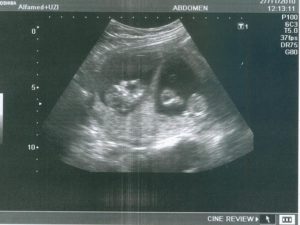

Первое УЗИ после удачного ЭКО назначают на 21–28 день после переноса (ДПП) плодного яйца. Но этот период зависит от клиники: некоторые врачи отправляют пациентку на ультразвуковое исследование только на 6 неделе после положительных результатов анализов. В этот период можно даже услышать сердцебиение плода, а сам эмбрион отлично просматривается на экране монитора.

- На 21 день после переноса эмбрионов врач уже может увидеть плодное яйцо, диагностировать благополучную беременность.

Первое УЗИ после ЭКО назначают на 21 – 28 сутки после экстракорпорального оплодотворения. Это стандартная процедура диагностики, позволяющая обнаружить не только беременность, но и положение ребенка, состояние организма будущей матери.

Обычно это 21-28-й день после переноса эмбрионов – если повышенный ХГЧ подтвердит факт беременности. В некоторых клиниках ультразвук после удачного ЭКО назначают только через 6 недель.

В это время эмбрион можно четко разглядеть на экране и даже услышать сердечко.В дальнейшем ультразвук проводится в те же сроки, что и при обычной беременности – в 11-14, 18-21 и в 30-32 недели. Но лечащий врач может и скорректировать график. Так, второй ультразвук часто рекомендуют уже через 1-2 недели после первого. А начиная со второго триместра УЗИ может потребоваться раз в 1-2 недели.

Начиная с 20 дня после эмбриональной подсадки врачом проводится УЗИ, которое дает возможность рассмотреть плодное яйцо полностью.В некоторых же диагностических центрах и клиниках первое ультразвуковое исследование назначают еще позже – примерно на шестой неделе. В это время можно уже четко разглядеть плод и услышать биение его сердца.